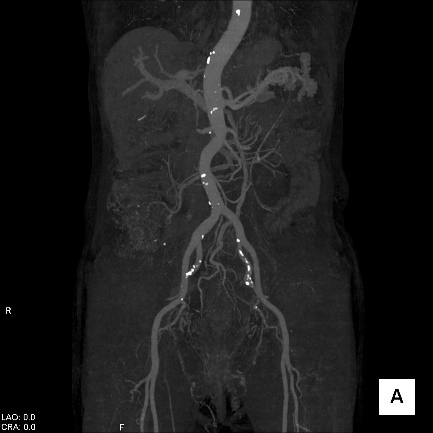

【CT(computed tomography)】

管球(ドーナツ状の部分にあるX線を出す機械)がX線を出しながら体の周りを回転し、人体を透過したX線をコンピューター処理して画像化します。短時間で広い範囲を撮影でき、様々な方向からの画像や3Dを作成します。